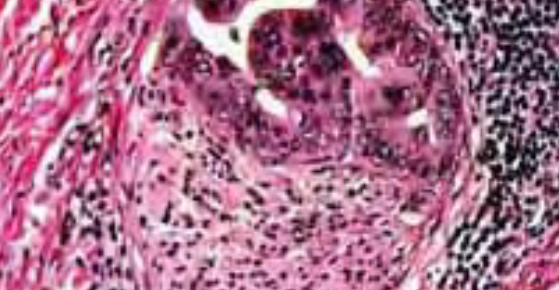

MATERIAL AND METHODS:Burn wounds were experimentally induced in two species of experimental animals which were treated with topically applied herbal preparation with concomitant monitoring of the healing process. Experimental groups (1) of 15 animals each (mice and rats), while control group (2) of 10 animals each (mice and rats) that were not being treated with herbal ointment. After the hair removal, burn was induced on the back of animals by heated brass seal. Different clinical symptoms including oedema of surrounding tissue, redness, exudation, size of the burn surface, histological and microbiological findings were monitored on the days 1, 3, 7, 14 and 21. A statistically significant difference was observed throughout descriptive statistics and paired Student's t-test.

CONCLUSION:Physiological healing processes of the acute burn wound following the topical application of herbal preparation can be monitored on the utilized animal model. A three-week treatment resulted in the 90% of completed epithelization in both animal species, indicating the effectiveness of topically applied herbal preparation.